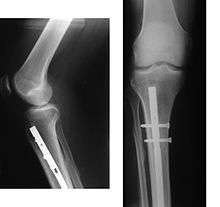

X-ray showing the proximal portion of a fractured tibia with an intramedullary nail.

Radiography to identify possible fractures after a knee injury.